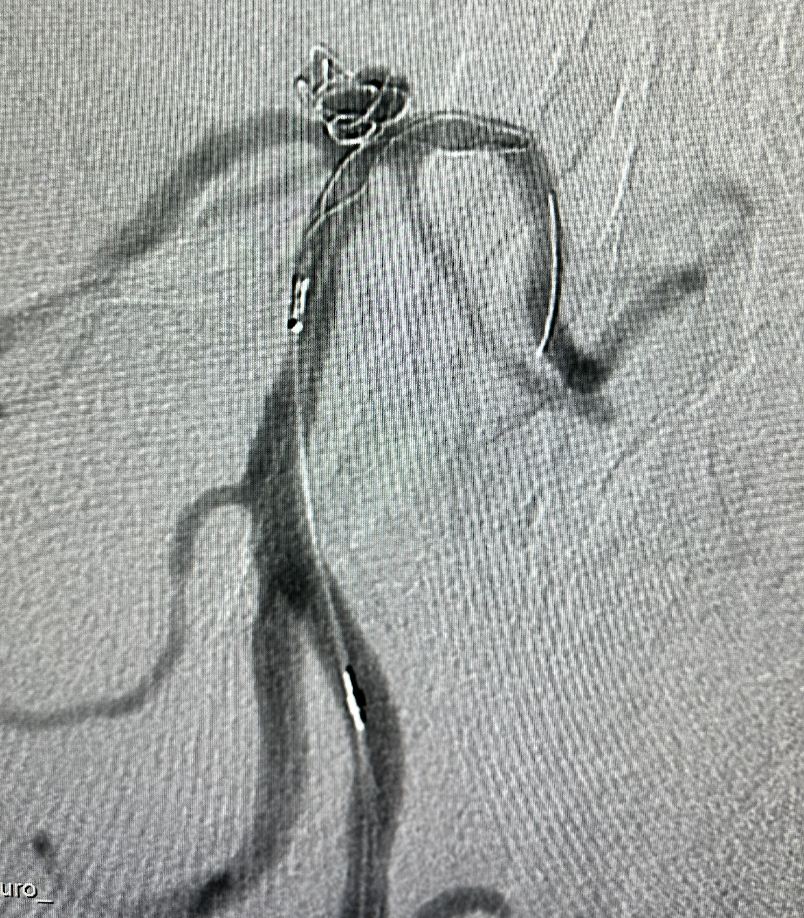

脑血管造影

基底动脉顶端动脉瘤,呈分叶状,瘤体5.6mm×3.6mm,瘤颈4.6mm

先将支架导管置入左侧大脑后动脉P2段,然后将直头微导管置入瘤体内,推出部分弹簧圈保护后半释放畅医达(TaminoVIA)颅内动脉瘤辅助栓塞支架

畅医达(TaminoVIA)颅内动脉瘤辅助栓塞支架 保护下,填充弹簧圈

继续释放并调整 畅医达(TaminoVIA)颅内动脉瘤辅助栓塞支架 至合适位置,支架两端为闭环设计,操作过程中能减少血管壁损伤,瘤颈处部分推密增加金属覆盖率

畅医达(TaminoVIA)颅内动脉瘤辅助栓塞支架完全释放,打开效果好,显影清晰,瘤体部分显影

术后造影显示动脉瘤囊闭塞,畅医达(TaminoVIA)颅内动脉瘤辅助栓塞支架形态良好,载瘤动脉通畅